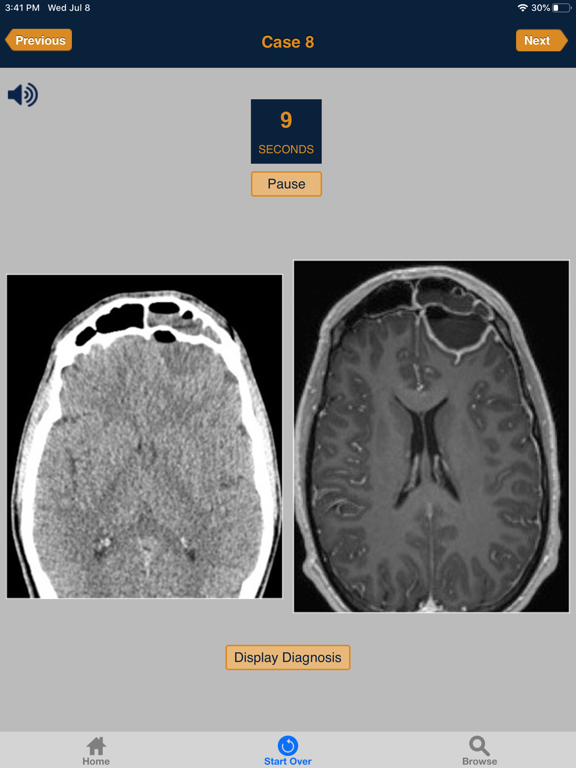

This App includes radiology images for 60 emergency cases that users must diagnose in 10 minutes. Each case is presented as an unknown. You have 10 seconds to make the diagnosis, before the answer is provided.